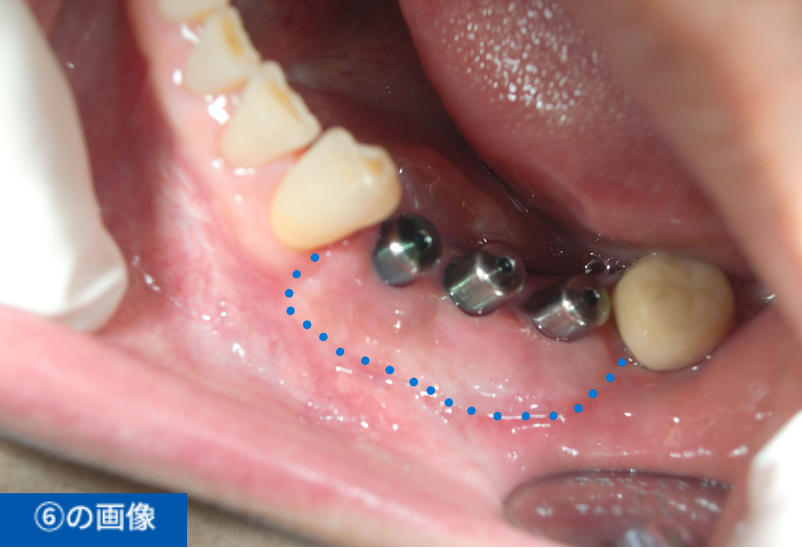

左下④56⑦番のブリッジの脱離にて来院(④⑦はブリッジの支台歯56は欠損)

| 費用 ※保険外診療 | 総額1,485,000円(税込) インプラント3本、手術2回、CGF、遊離歯肉移植、CT撮影、被せ物の型取り(印象)、被せ物(フルジルコニア)3本、投薬 |

| 想定されるリスク・副作用 | ・術後、痛みや腫れが生じる可能性があるが腫れは3日後がピークで徐々に治まる ・清掃状態が悪いとインプラント周囲炎(歯周病)を起こす可能性がある |